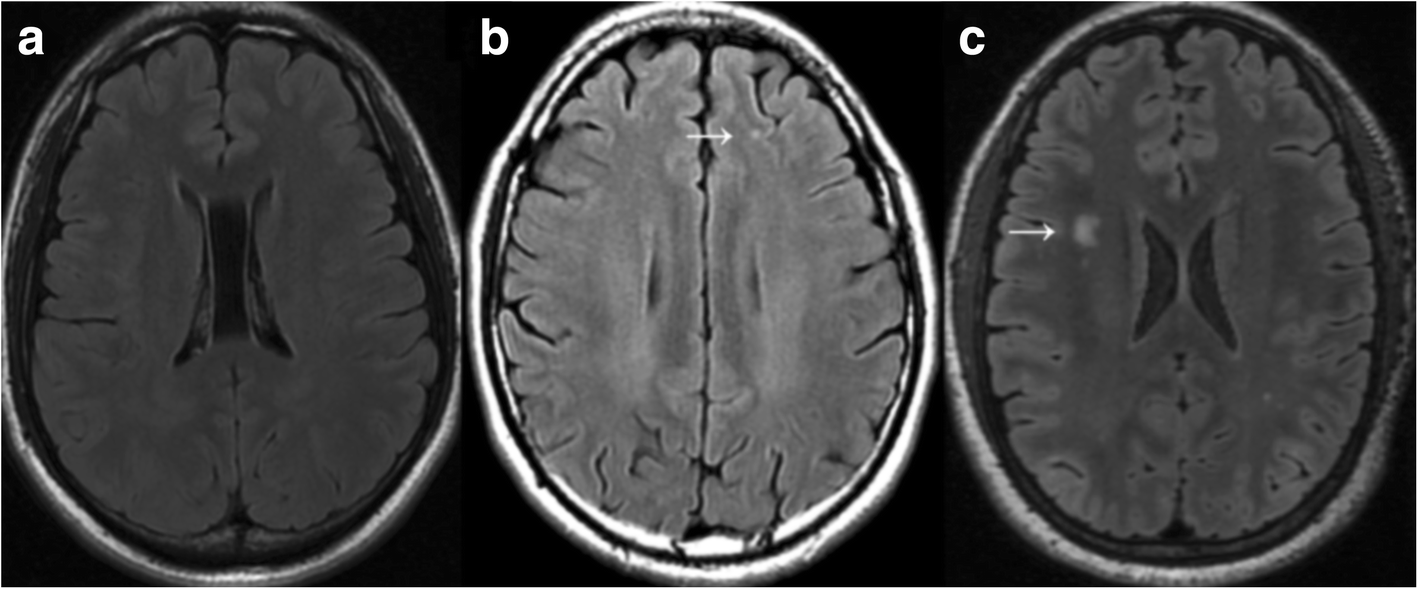

32+ White Spots On Brain Mri Migraine PNG. There are several causes of white spots on a brain mri, including small strokes, migraines, multiple sclerosis (ms), lupus, b12 deficiency, a brain. The white spots in the brain may indicate old age or areas which have been damaged.other tests may need to be done such as visual evoked potential i also have had bad headaches (migraines) and white spots were found on a ct scan and then later on a follow up mri.

Imaging Findings of Migraine

Imaging Findings of Migraine from img.medscapestatic.com

Sandra has since told daily mail australia that while 'some days are better than others' she is feeling a lot better and is regularly monitoring her health and checking in with. White spots on your mri. Mri can't diagnose migraines or headaches but it can rule out other medical conditions. Mri spots (white matter lesions) in patients with migraines.